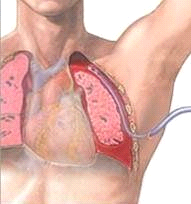

בחזה-אוויר הנובע מקרע של הריאה בלבד ללא פגיעה בבית החזה יש לטפל על-ידי ניקוזו בעזרת נקז המחובר לשסתום חד-כיווני או שקצהו מונח בבקבוק מלא מים ונמצא מתחת למים (Under water seal). כאשר לחולה חזה-אוויר בלבד מחדירים את הנקז ברווח הבין-צלעי ה-2 בקו האמצע בריחי. כאשר לחולה חזה-אוויר משולב בחזה-דם מחדירים את הנקז ברווח הבין-צלעי ה-4 בקו האמצע אקסילרי. הטיפול בחולים עם חזה-אוויר בלחץ הוא ביצוע מיידי של טורקוצינטזיס, על מנת לשחרר את הלחץ בבית החזה ולמנוע מוות. בחולה עם חזה-אוויר לאחר חבלה מחדירים את הנקז ברווח הבין-צלעי הרביעי (תצלום 15.16).

- הנקז מוחדר ברווח הבין-צלעי הרביעי בקו האמצעי של בית השחי (איור 9.16).

- הנקז יוכנס תמיד בסמוך לגבול העליון של הצלע התחתונה, על מנת להימנע מפגיעה בכלי הדם הבין צלעיים העוברים מתחת לצלע (איור 10.16)

- יש להקפיד בזמן החדרת הנקז, שכל החורים שבנקז יימצאו בבית החזה ולא מחוצה לו. חורים המצויים מחוץ לבית החזה יגרמו לחזה-אוויר פתוח. חורים המצויים בדופן יגרמו לאמפיזמה תת-עורית. יש להחדיר את הנקז לפחות 5–7 ס"מ מעבר לחור הקריבני

- יש לקבוע את הנקז לדופן החזה על-ידי תפר חזק בעור. הנקז מחובר לבקבוק מים מיוחד (Under water seal), הסגור הרמטית ומכיל בראשו 2 צינורות (איור 11.10- 12.16). האחד, אליו מתחבר הנקז, מצוי מתחת לפני המים, והשני, הקצר, מצוי מעל לפני המים. בעת הנשיפה יוצא האוויר החופשי מחלל הצדר דרך הנקז וממשיך דרך הצינורית הארוכה אל המים ומשם דרך הצינורית הקצרה החוצה. בעת שאיפה, האוויר אינו חודר לבית החזה מכיוון שהמים בבקבוק חוסמים את מעבר האוויר. בזמן השאיפה המים בצינורית הארוכה עולים בהתאם ללחץ השלילי המתפתח בבית החזה. תנועת המים בצינורית מצביעה על כך שמיקום הנקז הוא בבית החזה.